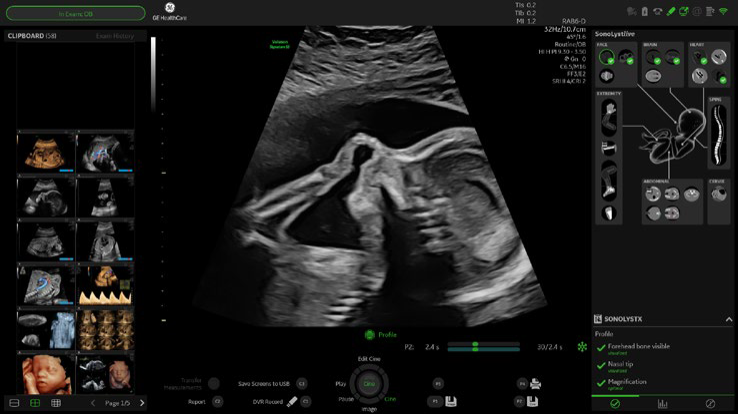

• AI based image guidance with SonoLyst*live

• Scan Assistant with SonoLyst image recognition